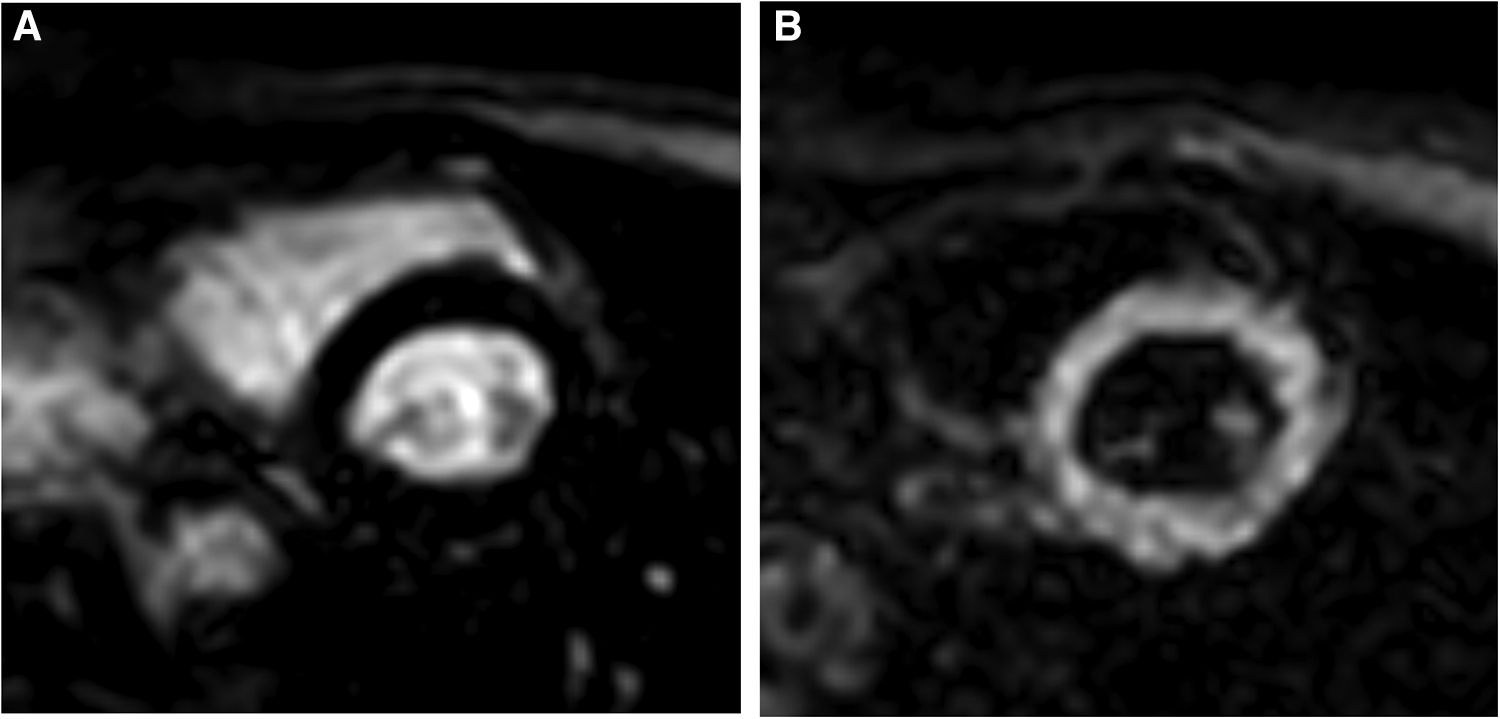

Figure 1

TI selection on the Look Locker sequence. (A) Typical inversion time utilized for conventional bright-blood LGE; blood pool is bright and myocardium is nulled. (B) Typical inversion time for gray-blood LGE; blood pool is nulled and myocardium is bright. TI for gray-blood LGE occurs prior to the typical TI for bright-blood LGE.